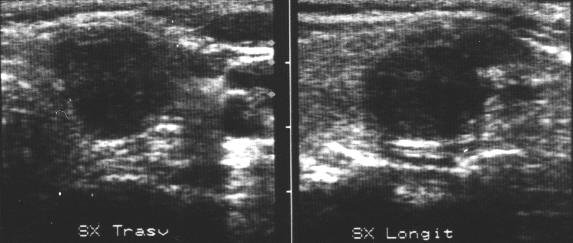

Femeie de 48 ani. Metastaza linfonodala

laterocervical stanga voluminoasa (14x26x32mm, 6 cc) de la neoplasm papilar

tiroidian.

Alta metastaza, mai mica ( 9x14mm), laterocervical stanga.

Citoaspiratie pozitiva pentru carcinom papilar.